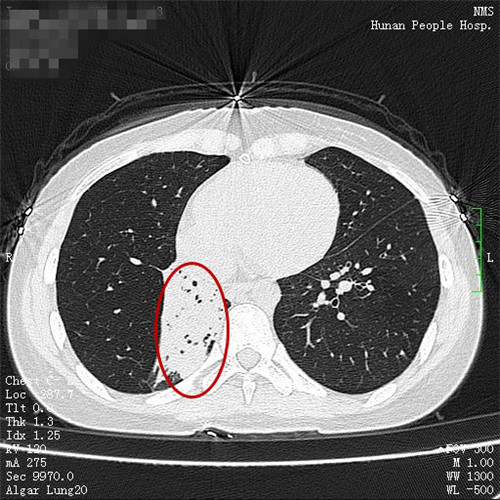

治疗前和治疗后

谭建龙副主任医师在接诊后通过详细的病史询问和体格检查,认为王女士很可能有肺结核合并气管支气管结核,立即进一步安排胸部CT检查和支气管镜检查,胸部CT检查发现其的右侧中间段支气管闭塞,右肺有2/3的肺被完全阻塞,支气管镜检查也发现右中间段支气管被大量的坏死物堵塞,多处气管都被病变累及,若不积极治疗,病变可能累及双肺,给病人造成不可挽救的伤害。

在呼吸科二病区接受了规律的全身抗结核治疗以及支气管镜下等介入冷冻治疗、药物灌注治疗后,王女士的气管、支气管病变得到控制,闭塞的右肺也得以恢复,咳嗽和呼吸困难症状也完全缓解。11月9日,王女士出院了,她心有余悸地说,没想到咳嗽居然是这么严重的疾病,应该早一点来医院的。